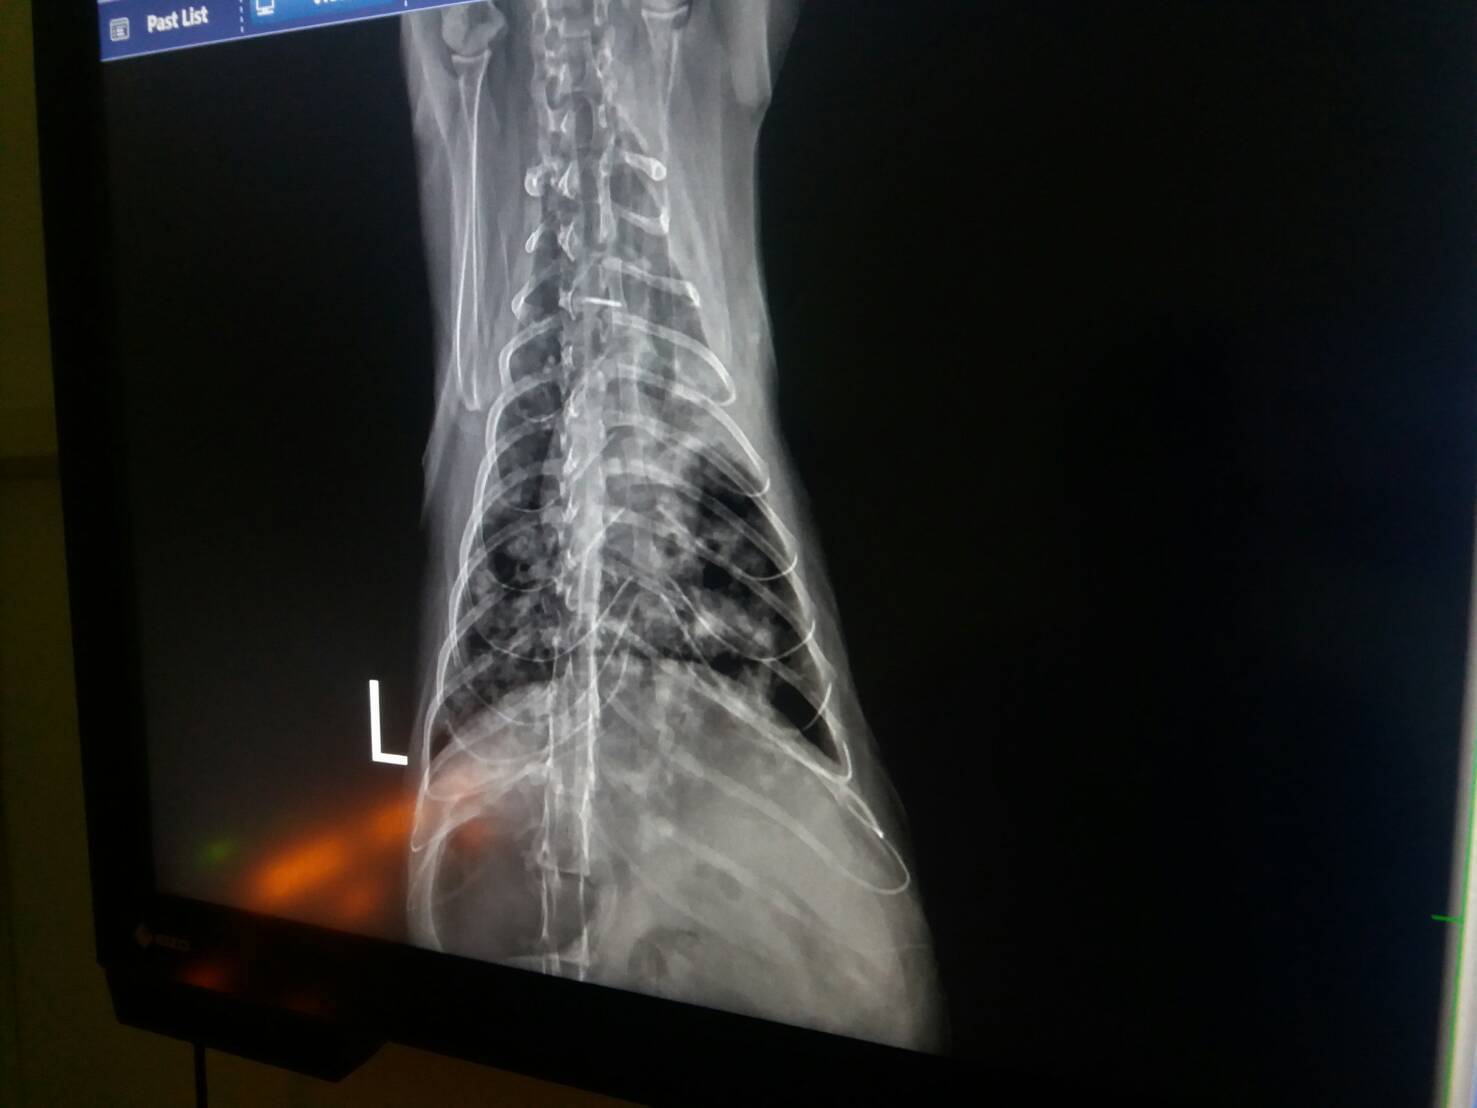

由X光下看見,小舞的肺部有感染發炎,也或許是急性的

若要追查原因則牽涉到需要做進一步解剖

即使肺臟功能有40%損壞,但外表上可能還不會表現

等到了50、60%了…才能夠觀察出有喘息的症狀